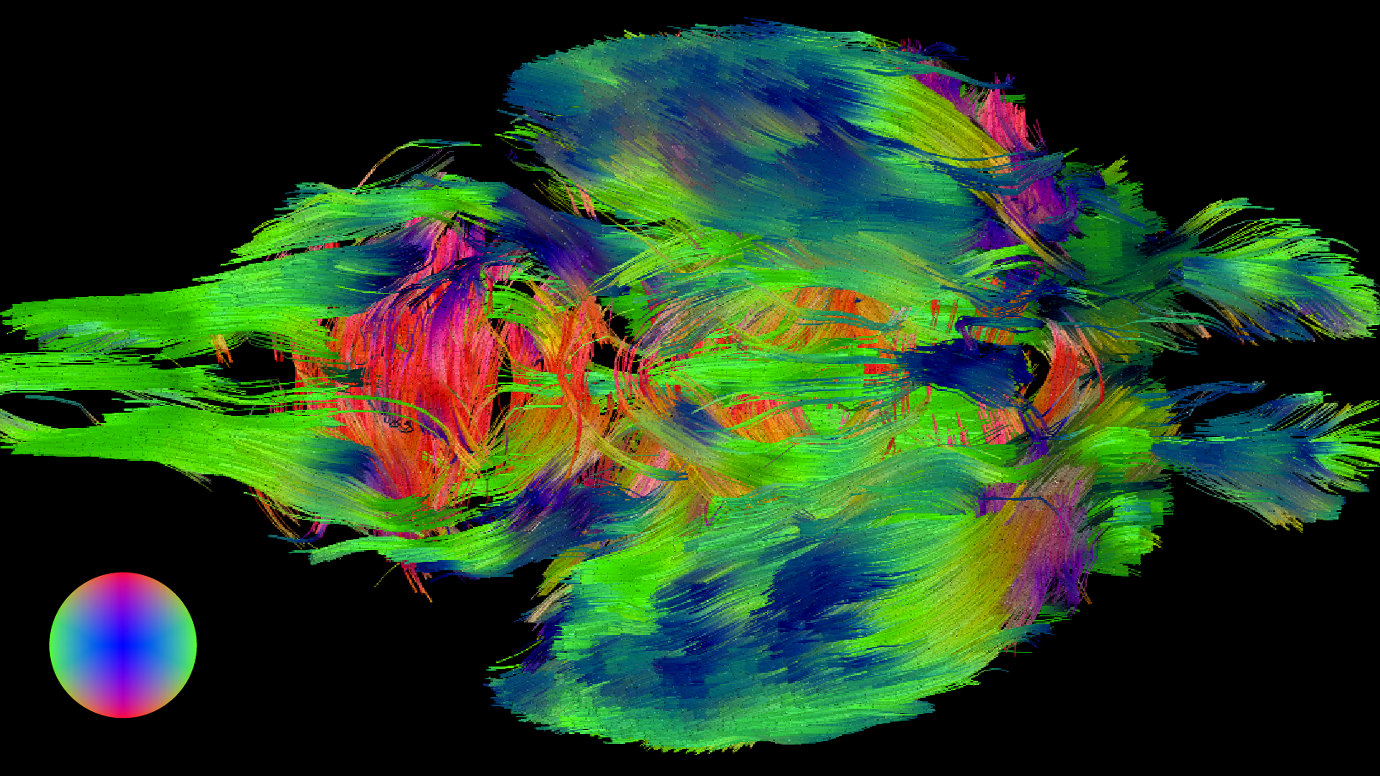

رایانه با قراردادن تصاویر میکروسکوپی کنار هم از برشهایی به ضخامت نانومتر یک تصویر سه بعدی ایجاد میکند.

ردیابی یک سلول واحد در چند برش مغزی و مشخص کردن سیناپس آن سلول. دندریت یک نورون به رنگ نارنجی با آکسون نورونی دیگر که با رنگ آبی مشخص شده است یک سیناپس برقرار کرده است.